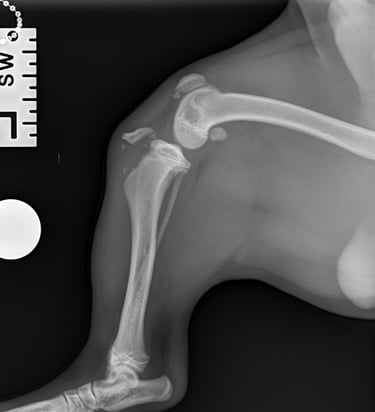

Case 5 - Bonnie

Tibia fracture - Mini Dachshund, 2y, female